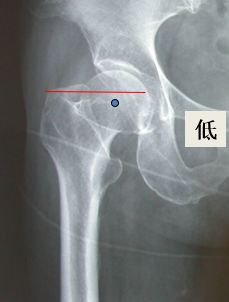

单看股骨侧,大转子顶点和股骨头旋转中心的关系恢复了

但髋臼旋转中心点上移了造成了患肢术后肢体短缩因此如果术中发现髋臼旋转中心点有上移或下移,股骨假体也应相应的吊高或下沉以获得双下肢等长

术后股骨头旋转中心点增高,导致患肢延长